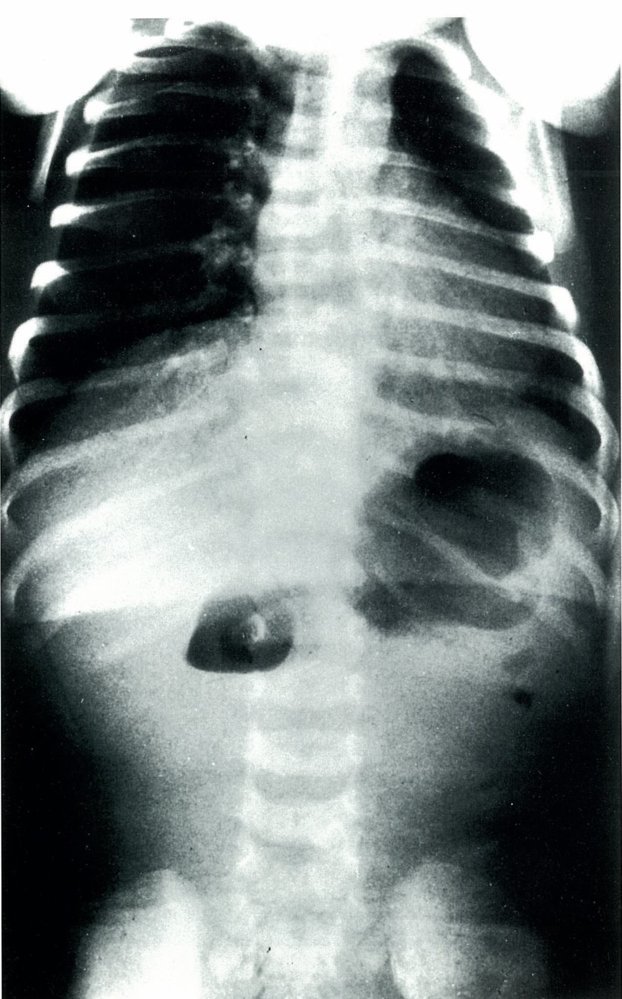

X-ray of the abdomen

Duodenal Atresia in a Newborn

(dilation of the pre-stenotic bowel segments (duodenum (D) and stomach (S)) with an air-fluid level in each dilated segment (double bubble sign). No air is visible in the post-stenotic bowel loops)